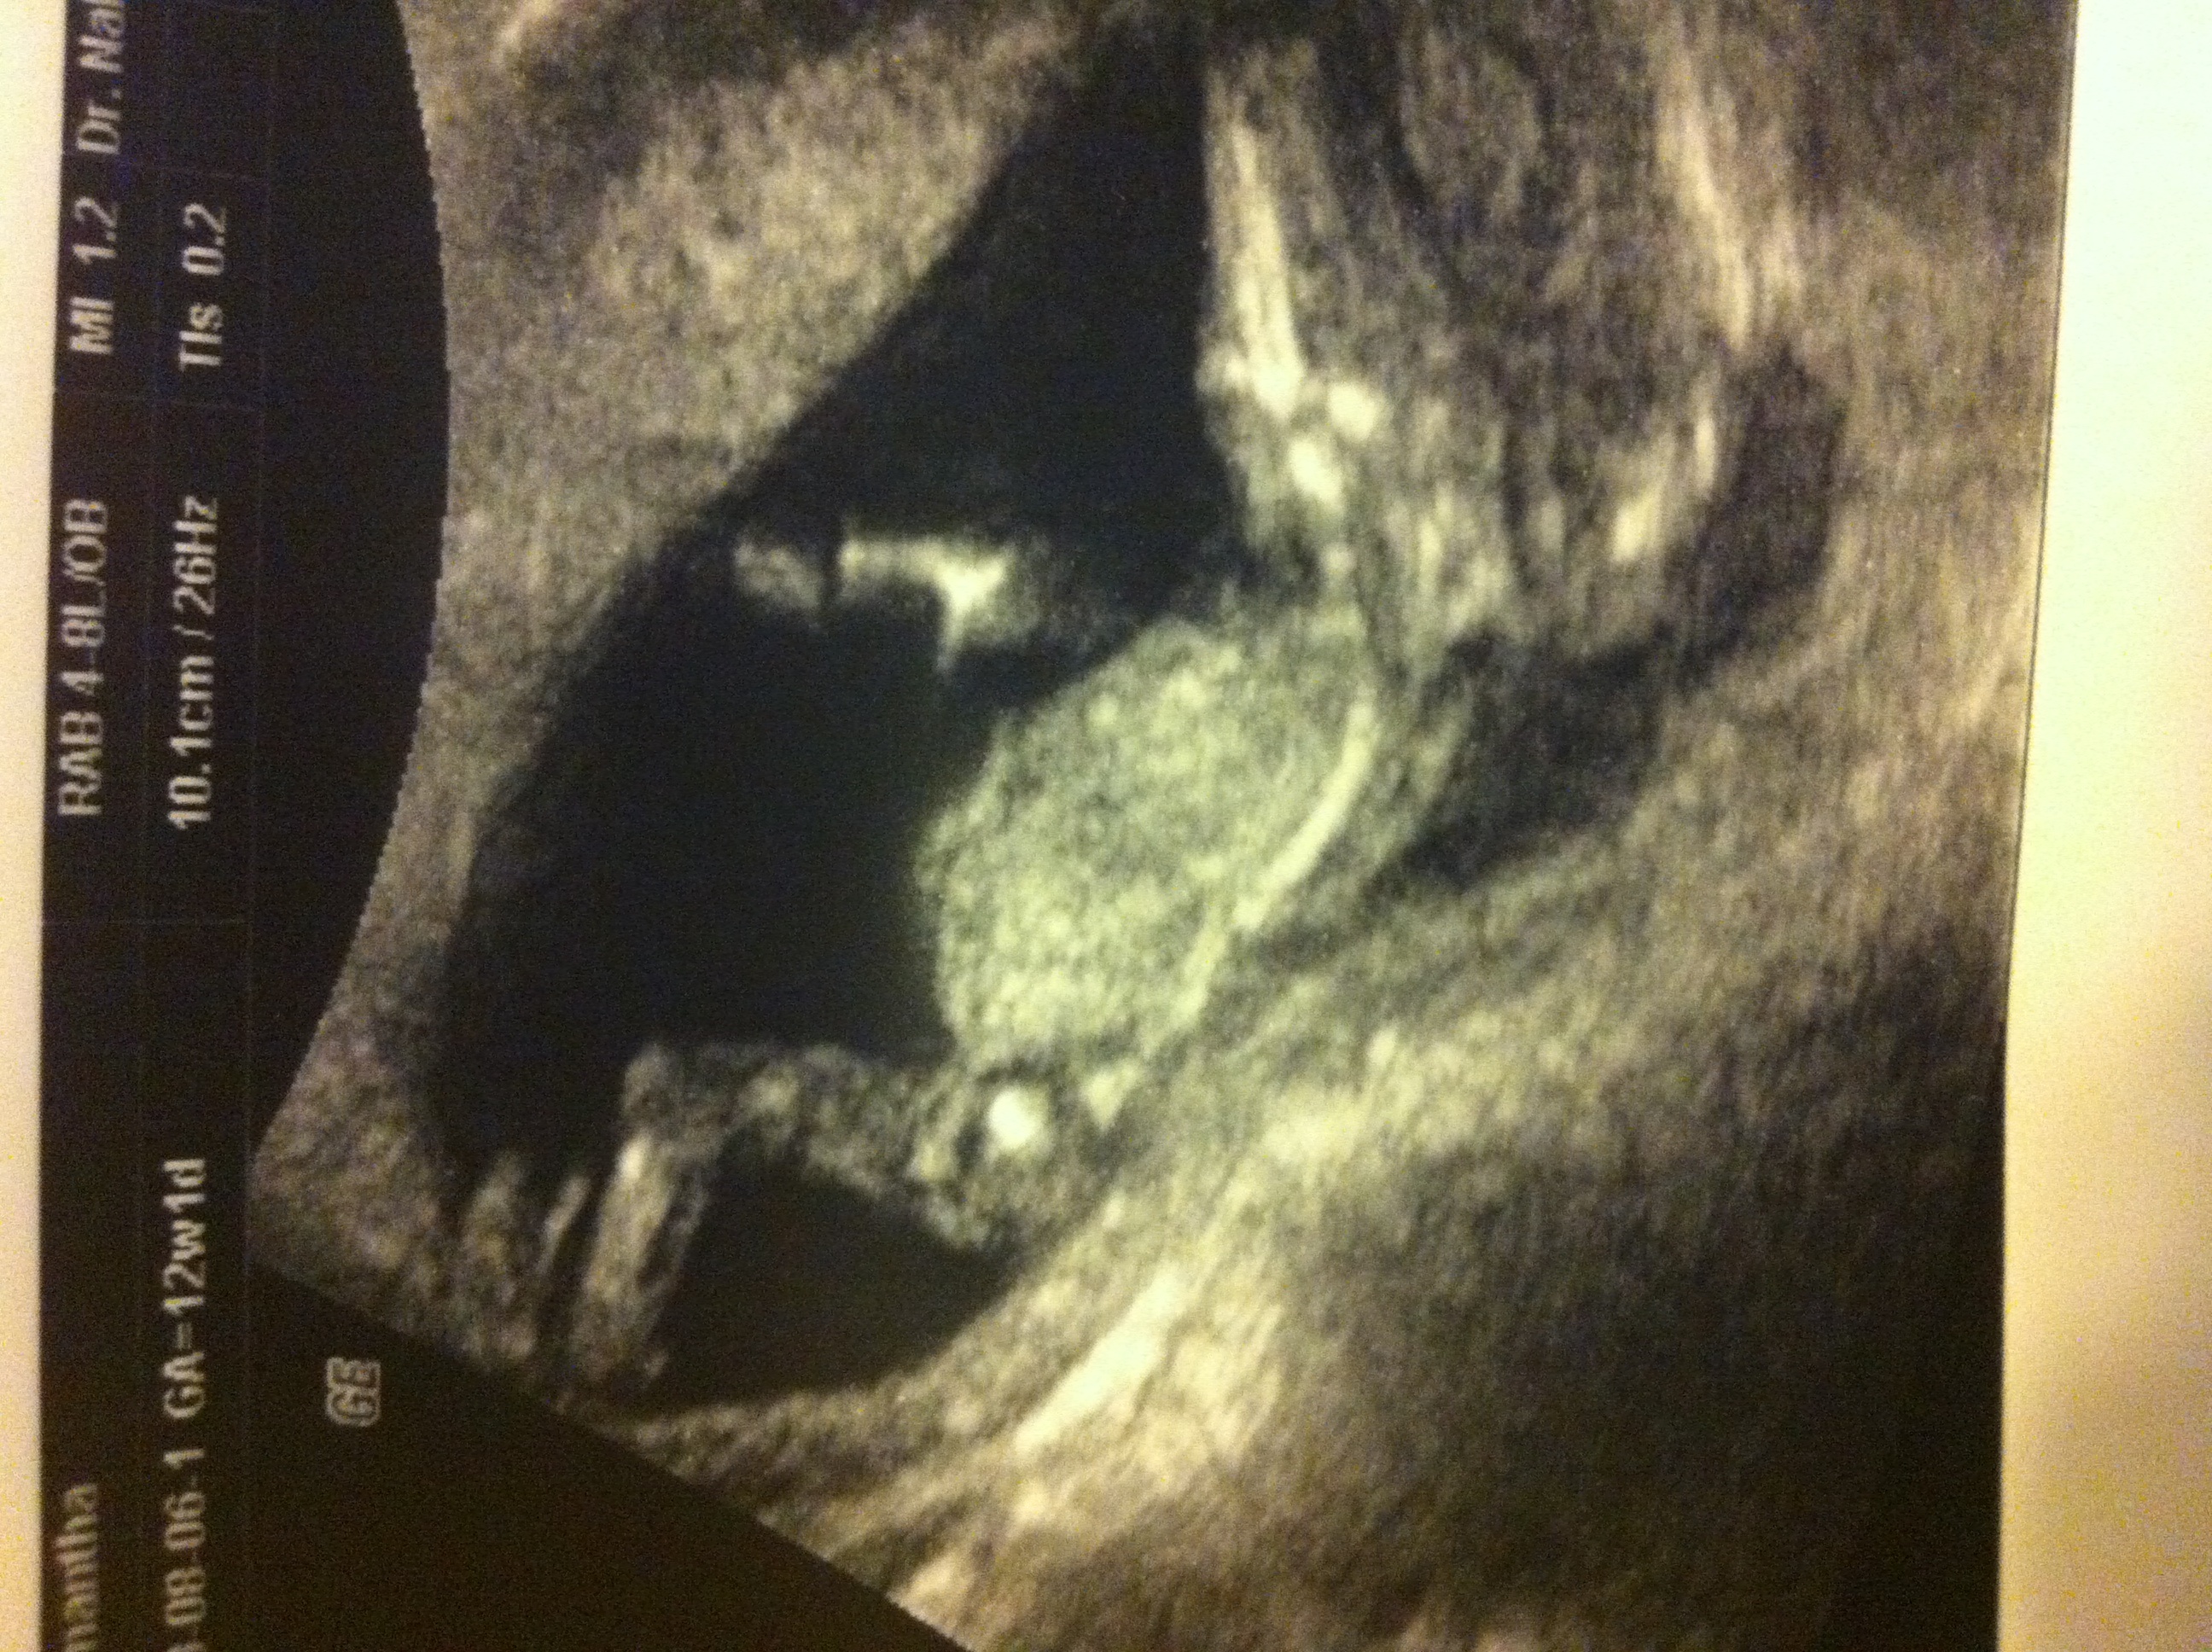

Am 12+2 today and had my NT scan. Both DH and I saw a straight forked line, but 10 mins later tech said boy and showed us these: also got a video on a disc but it is kicking up..

Notice on bottom picture the outline of what we meant we saw in the beginning.. It is a bit like Thorz first scan... But my other photoes look too blue..Attachment 12890Attachment 12891Attachment 12892